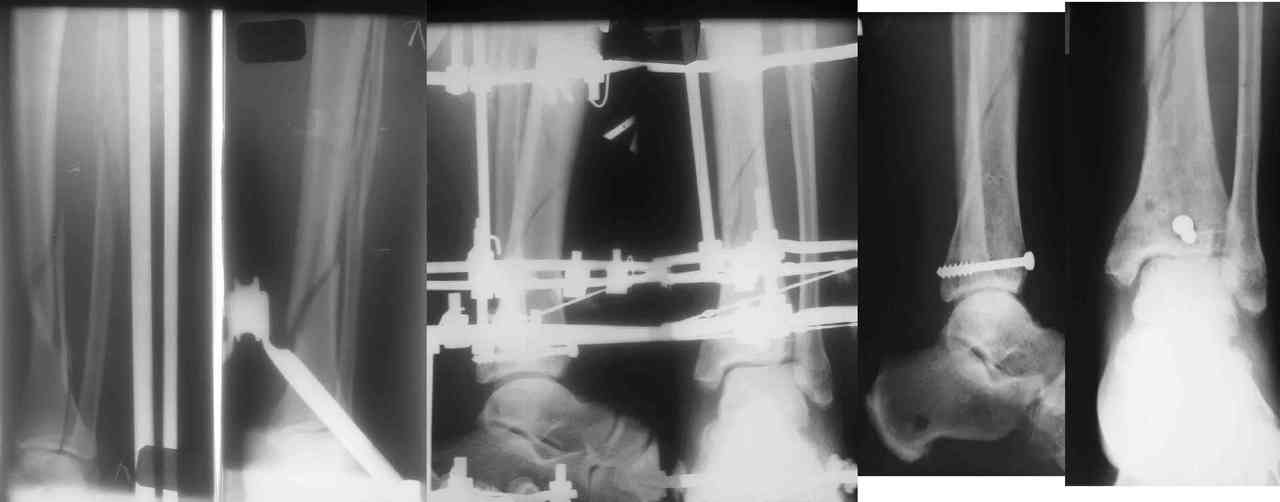

Во вложении - картинки из моей книжки как раз по этой теме

Схемы коррекции различных видов смещения в аппарате

Коррекция длины

Коррекция ротации

Коррекция ширины

В следующих письмах - дополнительные иллюстрации

Открытая репозиция.

Ничто особо не мешает, наоборот - все видно, требования к фиксации не очень высоки - можно просто фиксировать спицей или винтомю Внешний аппарат берет основную нагрузку

Пример -

задний край и диафиз

По поводу конкретного вопрошаемого случая:

1. Скорее всего в аппарате удасться вывести закрыто всё, кроме внутренней лодыжки. Открывайтесь и фиксируйте либо спицей с упором,

либо винтом.

2. ЭОП - очень спорное достижение в таких случаях. Сильные искажения.

Буквально вчера переделывали практически похожий случай. На ЭОПе всё идеально. На пленке - ступенька переднего края. Брали повторно, но уже

пригласили рентгенлаборантку в операционую сделать снимок.

3. Последнее время всё чаще делаем аппарат Илизарова в симбиозе с винтами, которыми фиксируем края (передний и задний), лодыжки и теперь - диафиз.

Позволяет пораньше снять аппарат.

Мы бы фиксировали пластиной м/берцовую кость открыто, на б/берцовую пластину MIPO, при необходимости сустав открыть минимально.

На фото простой суставной, метафиз. оскольчатый с переходом на диафиз перелом, пластина MIPO.